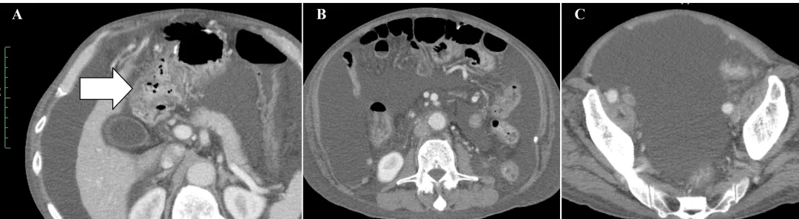

案例2:难治性宫颈癌转移灶消失,免疫功能恢复

小细胞未分化宫颈癌进展快、易耐药,预后极差。《Cureus》报道了一则突破性案例:一位 50 多岁的患者术后出现肝、淋巴结多处转移,化疗失败后,采用 WT1-DC 疫苗联合放疗: 1、第 67 天(注射第 5 剂疫苗后),CT 显示肝转移灶完全消失; 2、免疫指标(中性粒细胞 / 淋巴细胞比值等)恢复正常,原本因化疗受损的免疫功能显著改善。 案例3:胰腺癌患者中位生存期突破3年,7人成功手术 胰腺导管腺癌被称为 “癌王”,对放化疗天然耐药。《癌症免疫治疗杂志》的一项研究带来了新希望:10 例不可切除的胰腺导管腺癌患者(6 例 III 期局部晚期、3 例 IV 期转移性、1 例术后复发)采用 WT1-DC 疫苗联合化疗后: 1、所有患者肿瘤负荷下降,7人达到部分缓解,3人长期稳定; 2、9例患者中位无进展生存期 2.23 年,中位总生存期更是突破 3.52 年,远超传统治疗的预期。 3、 7 例成功接受了转化手术,其中 6 例实现 R0 切除(肿瘤完全切除,无残留),1 例为 R1 切除(镜下有残留)。 案例4:晚期十二指肠癌 4.3 年无进展,恶性腹水消失 十二指肠癌占胃肠道癌症的 0.3%-0.5%,虽发病率低但侵袭性强,易快速扩散,根治性手术是唯一可能治愈的手段,但晚期患者往往失去手术机会,且针对恶性腹水缺乏有效治疗方案。 《Cureus》曾报道一则案例:一位 72 岁的晚期十二指肠癌患者,腹膜播散伴恶性腹水,化疗失败后接受 WT1/MUC1-DC 疫苗联合细胞疗法: 1、第 8 次治疗后,恶性腹水消失,腹胀、水肿等症状消退; 2、原发病灶和转移淋巴结缩小,截至报道时,肿瘤 52 个月未进展,患者未出现严重副作用,且能正常活动。 锐赛EP-DC(医迪泰)是一种通用型的DC细胞疫苗,可靶向激活免疫系统对22种常见肿瘤抗原的免疫反应。产生强大免疫应答(CD4+/CD8+)识别所有肿瘤抗原,并覆盖广泛HLA类型。 当向患者给药时,医迪泰诱导的免疫应答有可能识别及破坏体内的癌细胞并向免疫系统持续提供支持和记忆,以便其能够持续靶向及预防癌症复发的可能。 2025年初,顶尖期刊Small Science(IF 12.7)发表了yl6809永利官网首席科学家范小勇教授与复旦大学附属上海市公共卫生临床中心研究组、南方科技大学附属深圳市第三人民医院/国家感染性疾病临床医学研究中心研究组的合作研究,题为“Dendritic Cell Vaccine Harboring Inactivated Mycobacteria Induces Immune Protection Against Tuberculosis in Murine Models and is Well Tolerated in Humans”。 本研究在上海市重大传染病和生物安全研究院官网的报道 该项临床研究使用了锐赛自主知识产权的新一代EP-DC疫苗技术。此前,这一创新技术已在多项抗肿瘤、抗HPV病毒治疗的临床研究中被证明有效。本次研究是EP-DC技术在结核病临床研究的重磅亮相。 yl6809永利官网负责制备DC 范小勇教授团队的突破性研究,首次证实DC细胞应用有望成为预防和治疗结核病的新策略。同时也揭示了新一代EP-DC疫苗技术可以在感染疾病的全病程治疗中发挥重大作用。 随着论文的发表,说明锐赛新一代EP-DC疫苗技术的应用场景已从肿瘤治疗的最后防线,扩展至疾病预防、病原微生物清除、病理进展逆转、疾病辅助治疗和术后防复发的全流程。